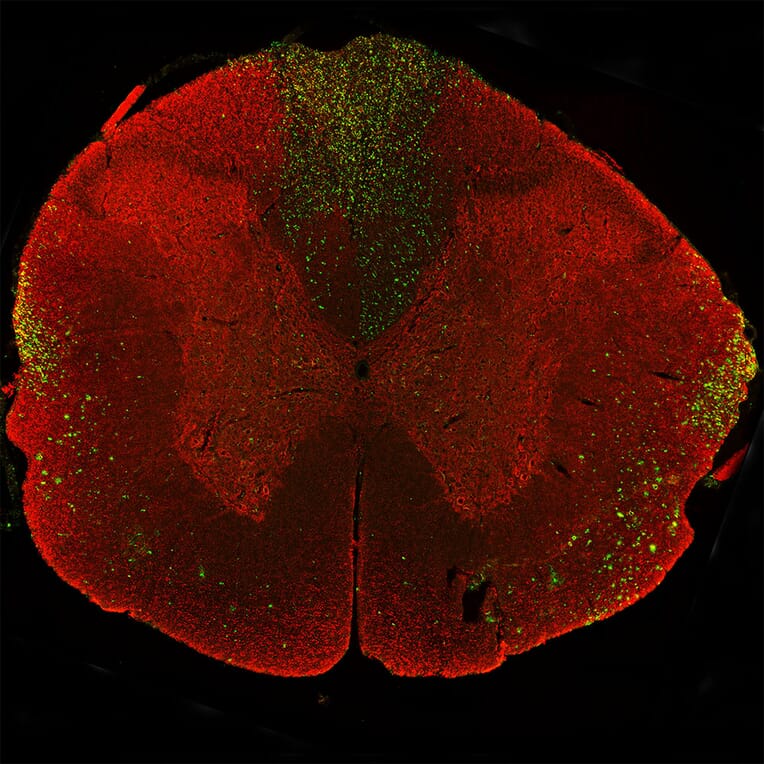

Immunostaining of a coronal section of the spinal cord of a rat given a midline C4 contusion injury three days previously. Sections were stained with Anti-NF-L Antibody (A270580) (red) and Anti-NF-L Antibody [6H63] (A333276) (green). Anti-NF-L Antibody [6H63] (A333276) stains prominent aggregates of material concentrated in the lateral funiculi and the dorsal columns but seen in lesser amounts throughout the section. These are degenerating and degenerated axons damaged by the C4 lesion. The Anti-NF-L Antibody antibody binds the C-terminal “tail” region of NF-L which is absent or destroyed during degeneration, so the positive profiles are largely negative for Anti-NF-L Antibody.